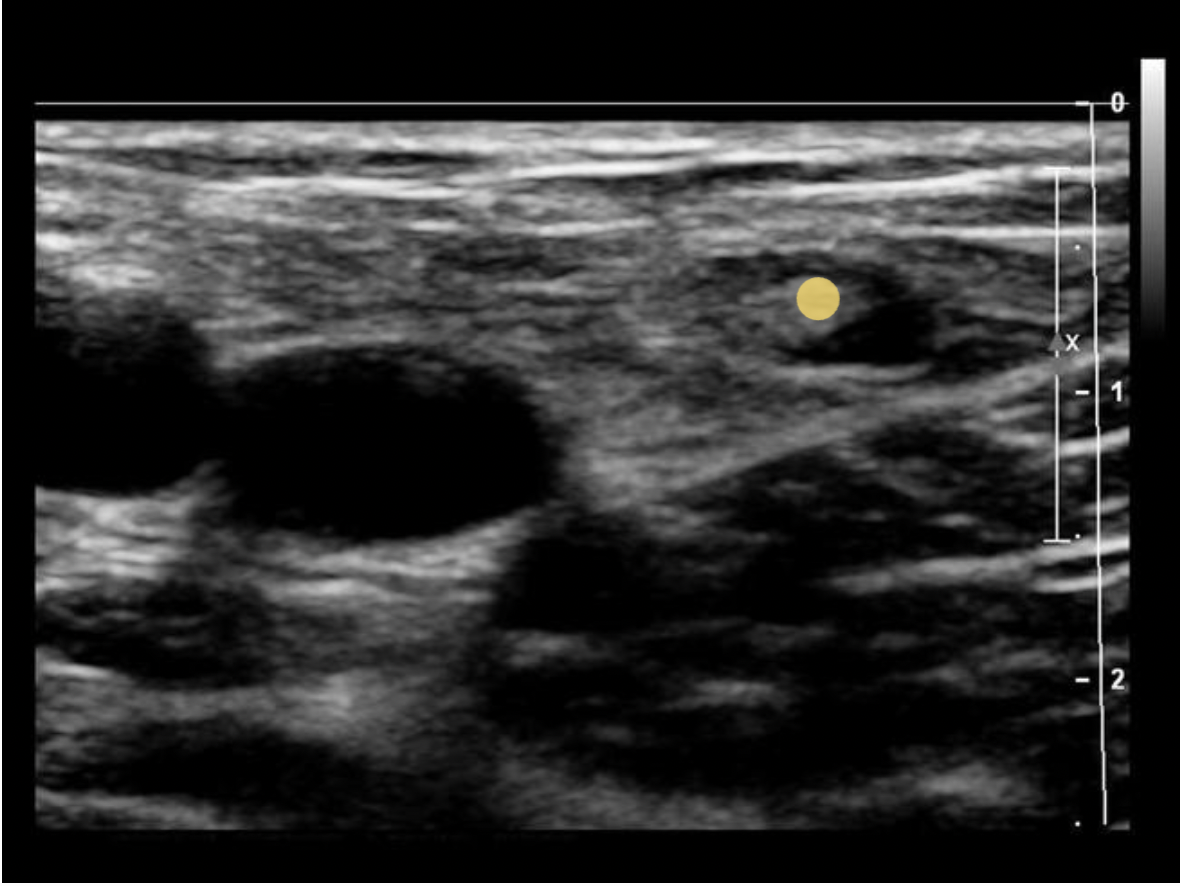

Which of the following is a characteristic of a normal lymph node?

A. posterior enhancement

B. round shape

C. thin hypochoic rim with hyperechoic central hilum

D. thick hypochoic rim with hypervascularity

Normal lymph nodes are ovoid in shape. They do not demonstrate posterior enhancement. As lymph nodes enlarge with abnormal fluid accumulation, they appear more rounded and hypochoic/anechoic. The "plump" cortex causes decreased visualization of the central hilum. Color Doppler can be used to locate the hilum and main vascular supply. Posterior enhancement is present in structures posterior to abnormal nodes with significant fluid accumulation.

Find the normal lymph node

A normal lymph node is oval in shape and demonstrates a thin hypoechoic rim of tissue around an echogenic hilum. Abnormal lymph nodes demonstrate a more rounded shape, thickened cortex that can appear anechoic. and there is loss of differentiation of the hilum.